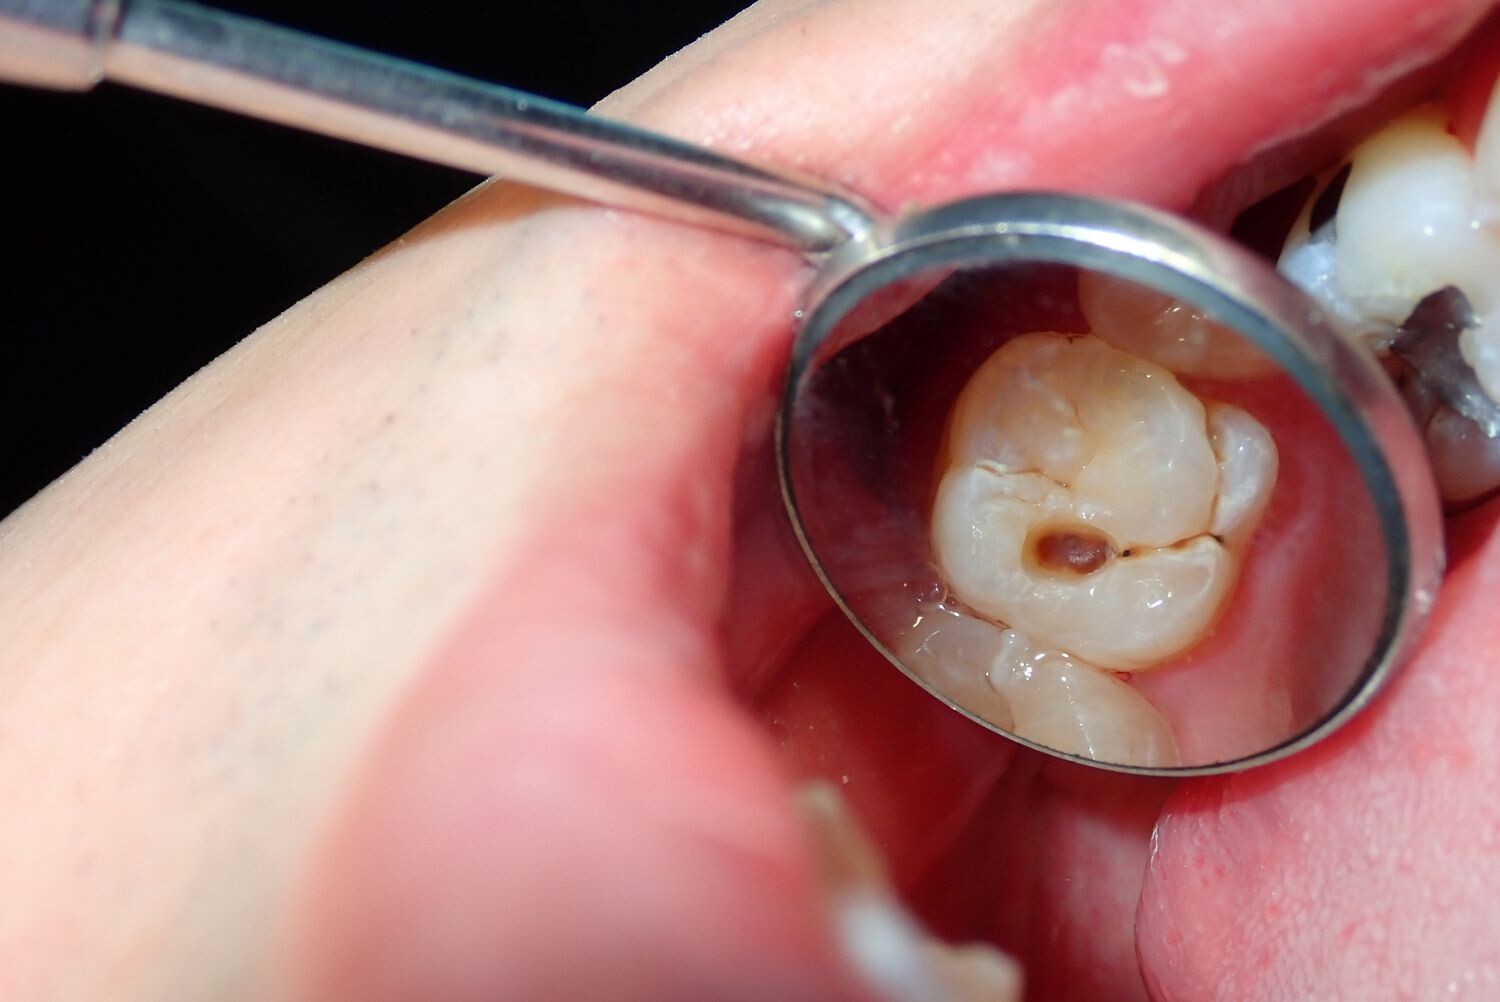

Signs of a Cavity

What does a cavity feel like? In the earliest stages, the answer might be nothing. There are no nerves in your tooth enamel, so when the decay is in that layer, you likely won't feel a thing. Once the decay has progressed enough to reach the softer tissues inside the tooth, where the dentin and nerves are, you might notice signs of a cavity. Your teeth might feel sensitive and you could feel some pain, especially after eating sweets, hot foods or cold foods. The pain can be fairly mild or sharp and intense. Some people with cavities also feel pain when biting down.

Depending on the size of the cavity, you may be able to see evidence of it in your mouth. Cavities sometimes create visible holes in the teeth. They can also create stains that are black, brown or white on the surface of the tooth.

What should you do if you think you have a cavity? The first step is to see your dentist. Although cavities can be reversed in the early stages, by the time you are feeling discomfort or pain, only a dentist can treat them. An x-ray will be taken to determine how the cavity has progressed into the tooth. Depending on how severe the cavity is, you might need a filling to fix it. If the decay is very severe, the dentist might replace the tooth with a crown or perform a root canal.